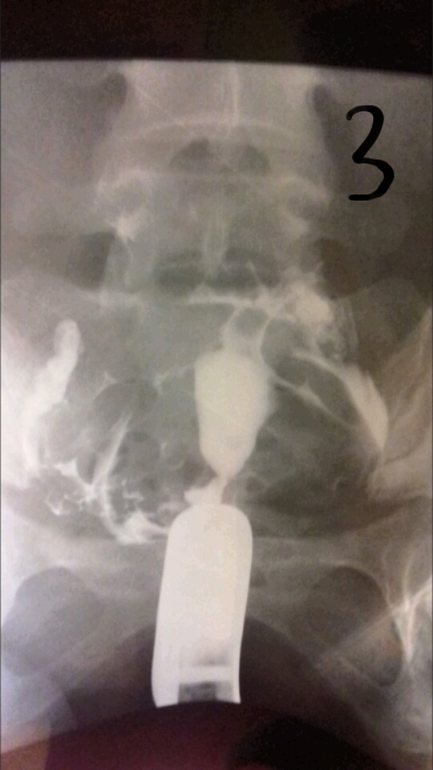

ГСГ, ЭХО, МСГ, ФертилоскопияВсем привет. Кто понимает в снимках. Сделала гсг. На третьем сказали жидкость вышла, но как-то долго она выходила и спайки видно, поставили эндометриоз и спаечный процесс в брюшной полости. Беременность не наступает и стимуляции были. В 2006 году было кесарево и в 2012 прижигали эррозию ш/м, больше ничего.